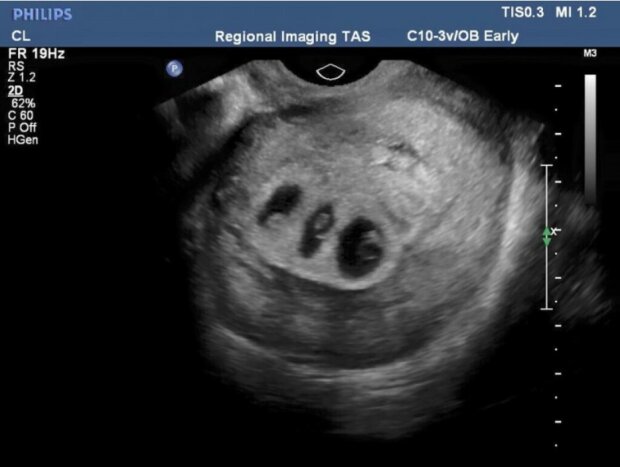

Břicho se zvětšovalo velmi rychle. Bylo tak obrovské, že žena měla problémy s pohybem. Neodkladná návštěva lékaře a ultrazvukové vyšetření vyjasnily situaci.

Žena čekala trojčata. Pro pár to byla šokující zpráva, protože to znamenalo, že budou vychovávat šest dětí! Ukázalo se také, že jedním z tří dětí bude vytoužená holčička. Dva kluci se vyvíjeli dobře, ale holčička slábla. Její plíce neměly dostatek kyslíku, což mohlo způsobit její smrt.